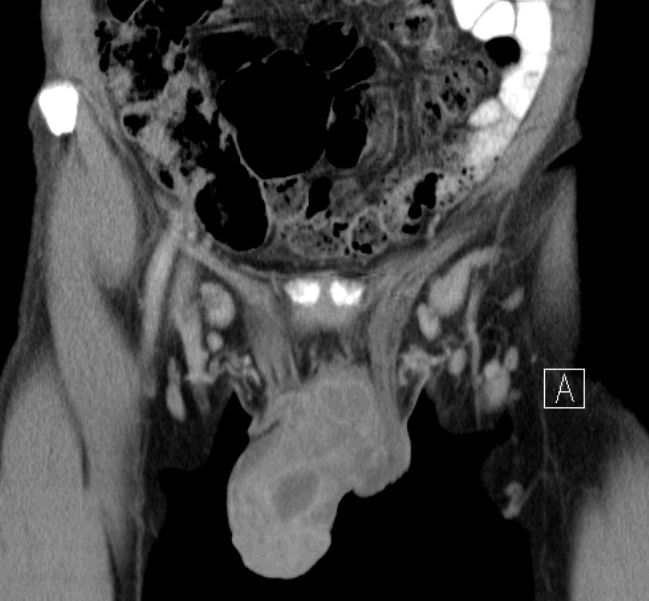

65-jähriger Mann mit fortgeschrittenem Peniskarzinom. Glans und Corpus callosus befallen.

inguinale Lymphknotenmetastasen gut sichtbar.

symmetrische inguinale Metastasen